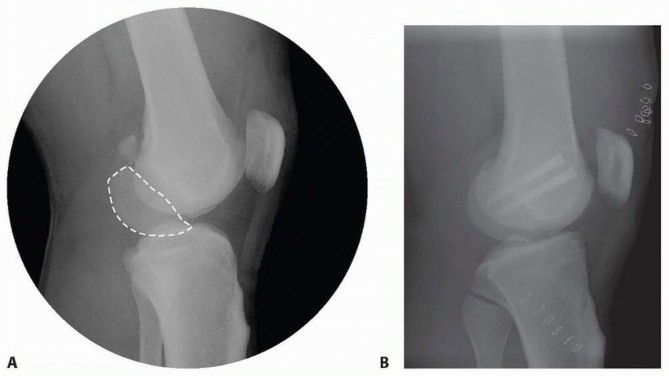

### FIG 10 • A,B. AP and lateral radiographs of an elderly patient with multiple comorbidities with an extra-articular distal femur fracture (AO type A; an incomplete intercondylar split— red dashed arrow). C,D. Postoperative radiographs showing stabilization with retrograde intramedullary nail. E,F. One-year postoperative radiographs showing a healed fracture with some subsidence of the metaphyseal region and mild protrusion of hardware through the notch. Ninety-five-degree condylar screw Ninety-five-degree blade plate Nonlocking plates with or without medial support (medial plate or external fixation) Limited internal fixation Limited fixation with screws only can be used for partial articular type B, especially type B3. The amount of open reduction required depends on the adequacy of closed reduction techniques and obtaining an anatomic reduction of the joint surface. Headless screws are useful for type B3 fractures in which the screws have to penetrate the joint surface ( FIG 12). Countersinking the screw heads can also be performed. Biomechanics of fixation: implant considerations There has been concern that the newer locking plate constructs are too stiff, resulting in inconsistent and asymmetric callus formation. 9 Some clinical evidence show less callus formation with stainless steel plates versus titanium plates. 9 Conversely, a biomechanical study has not shown a significant difference mechanically between constructs of stainless steel LISS plates with bicortical screws or titanium LISS plate with unicortical screws.1 474

--- - FIG 12 • A. Lateral radiograph of patient with a grade II open distal medial femoral condyle fracture (type B3). The Hoffa fragment is outlined. B. Postoperative radiograph after fixation with headless screws, buried underneath the subchondral bone. Soft tissue dissection should be limited. Adequate exposure is important to anatomically restore the articular surface. Restoration of limb “anatomy” must be accomplished and allow early range of motion. Stable internal fixation and length and sizes of implants should be templated. Radiographs of the injury can be templated with implant templates to ensure that proper lengths are available. A tentative plan of the fixation construct can be drawn on the image. Additionally, “preop planning” of the operating room should be performed; this includes a discussion with the operative team about the positioning and equipment needed for the procedure. The need for bone grafting or the use of bone graft substitutes should be assessed. Fracture fragments and the anticipated fixation construct should be templated. The surgeon should check for coronal plane fractures of the condyles (also known as Hoffa fragments) (see FIGS 5C and 6). 476